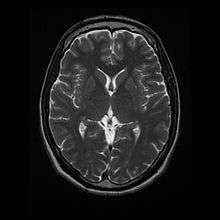

- T1: Cerebrospinal fluid is dark. T1 weighting is useful for visualizing normal anatomy.

T1 (note CSF is dark)